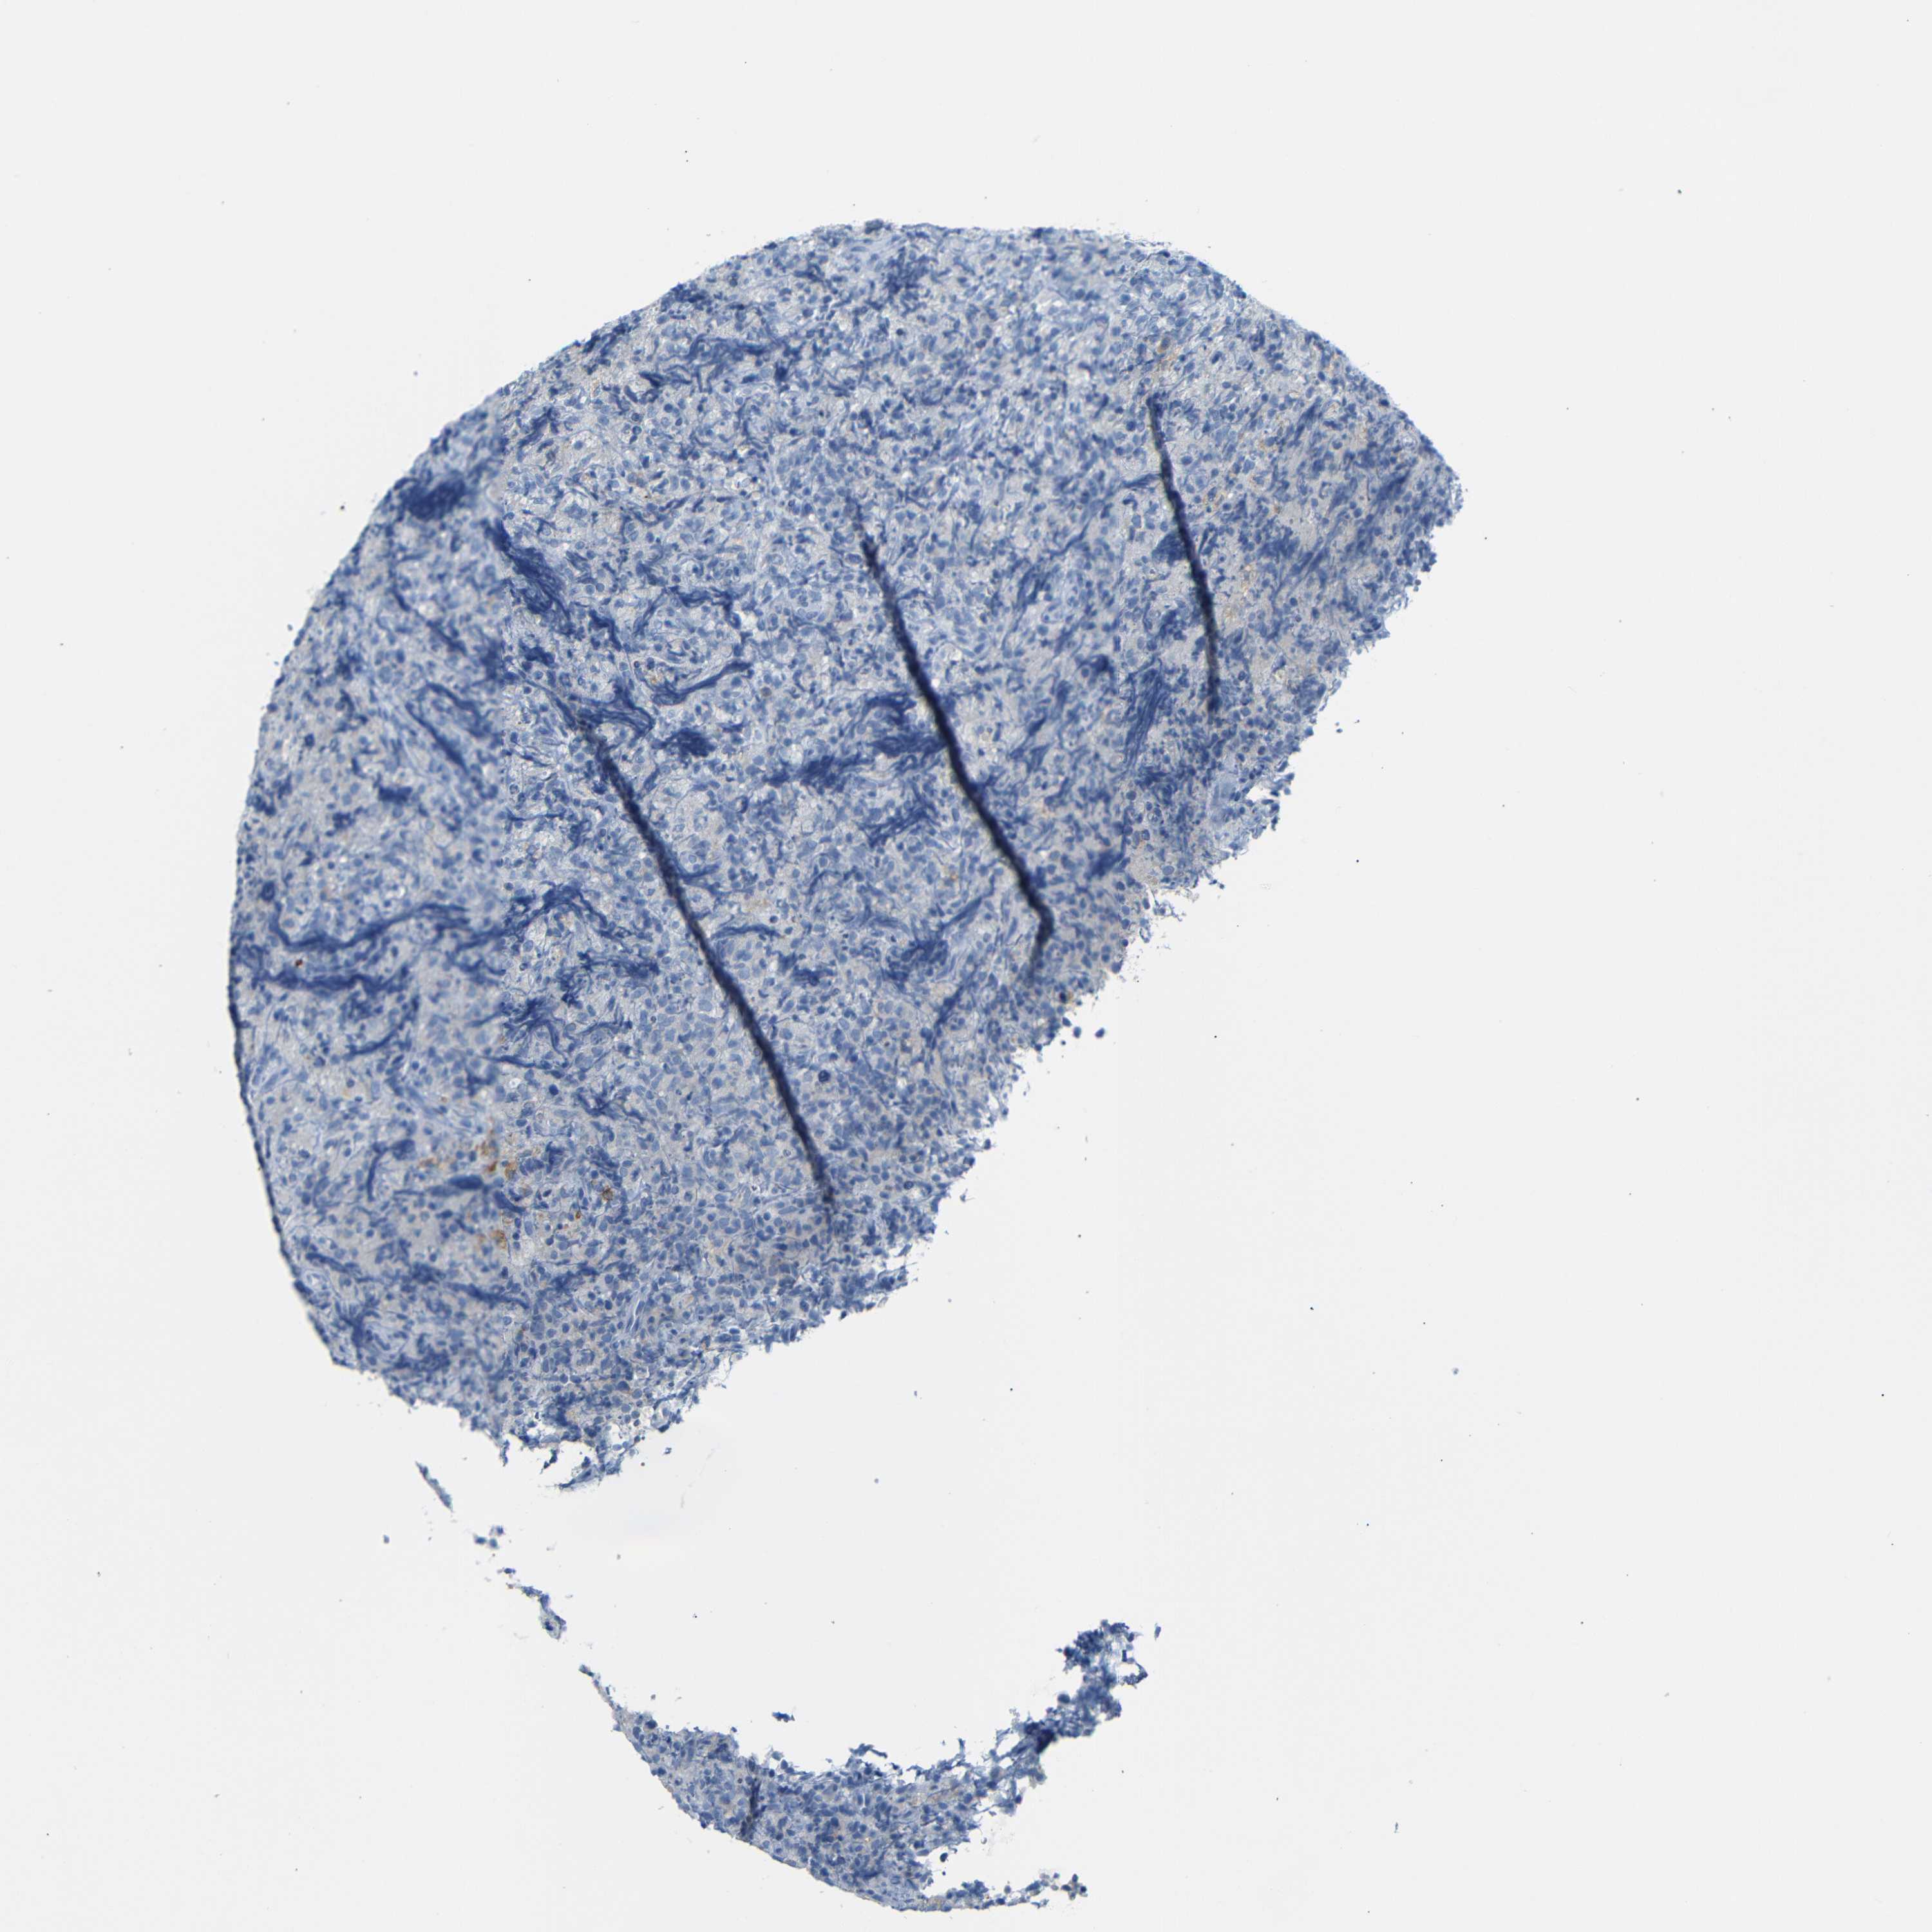

LYMPHOMA - Protein expressioni

A mouse-over function shows sample information and annotation data. Click on an image to view it in a full screen mode. Samples can be filtered based on level of antibody staining by selecting one or several of the following categories: high, medium, low and not detected. The assay and annotation is described here.

Antibody stainingi

Antibody staining in the annotated cell types in the current human tissue is reported as not detected, low, medium, or high, based on conventional immunohistochemistry profiling in selected tissues. This score is based on the combination of the staining intensity and fraction of stained cells.

Each image is clickable and will lead to virtual microscopy that enables deeper exploration of all samples and also displays staining intensity scores, fraction scores and subcellular localization as well as patient and tissue information for each sample.

Antibody HPA013323

Hodgkin's disease, NOS

Malignant lymphoma, non-Hodgkin's type, High grade

Malignant lymphoma, non-Hodgkin's type, Low grade